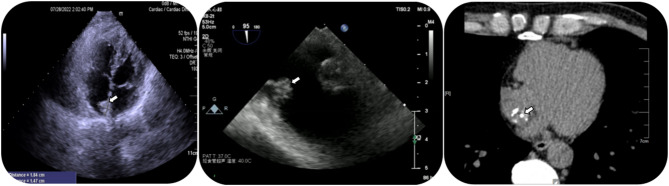

Case presentation: An asymptomatic 46-year-old male was discovered to have a cardiac mass upon echocardiograph. Echocardiography revealed a 13.2 × 11.8 mm pedunculated mass in the right atrium, attached to the interatrial septum. Then we performed surgical treatment. Histopathology revealed some myocardial tissue, a powdery stained, calcified amorphous area, and a few localized lymphocytes and red blood cells. The final diagnosis confirmed a cardiac CAT.